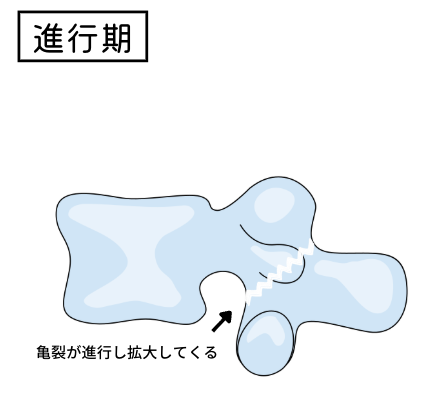

分離症には「初期」「進行期」「終末期」の3段階に分かれています。

ステージ2は「進行期」と言われ、亀裂がハッキリとしてくる時期。進行期の中でも、痛み始めて前半なのか、痛んでしばらく時間が経っているかで治癒期間がかなり変わります。最低でも2~3ヶ月の安静期間をとり、それでも回復傾向が見られなければさらに数ヶ月の安静が必要となります。かなり長い戦いになりますが、進行きはまだ骨がくっつく可能性が残されています。